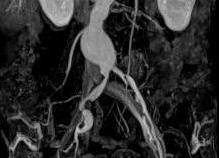

МРТ тонкого и толстого кишечника. Гидро МРТ. Колоноскопия

Существует множество эффективных и достоверных методов выявления патологий желудочно-кишечного тракта. Самыми информативными считаются гидро МРТ, колоноскопия и ирригоскопия, о которых и пойдет речь.